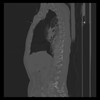

30 CUERPO,CE,Sagittal,3.000,CUERPO,Sagittal,